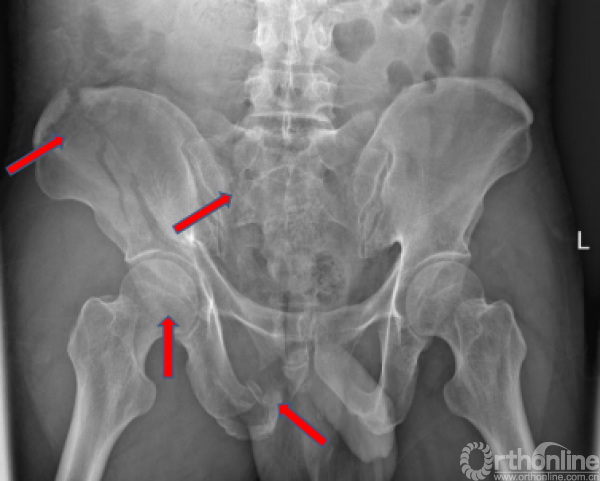

术前X线(2017.09.17)

骨盆正位、骨盆入口位、骨盆出口位

骨盆骨折,右侧骶骨骨折;

右侧髋臼骨折;

骨盆AO和Tile分型,以及基于骨折的受伤机制和稳定性Young and Burgess分型:APC LC(lc-II型)、VS、CM;髋臼两类十型(前柱合并前壁);骶骨骨折Dennis分型(II区)